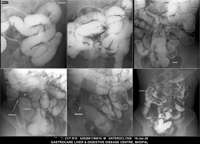

Section: ENTEROCLYSIS

Total: 205 Cases